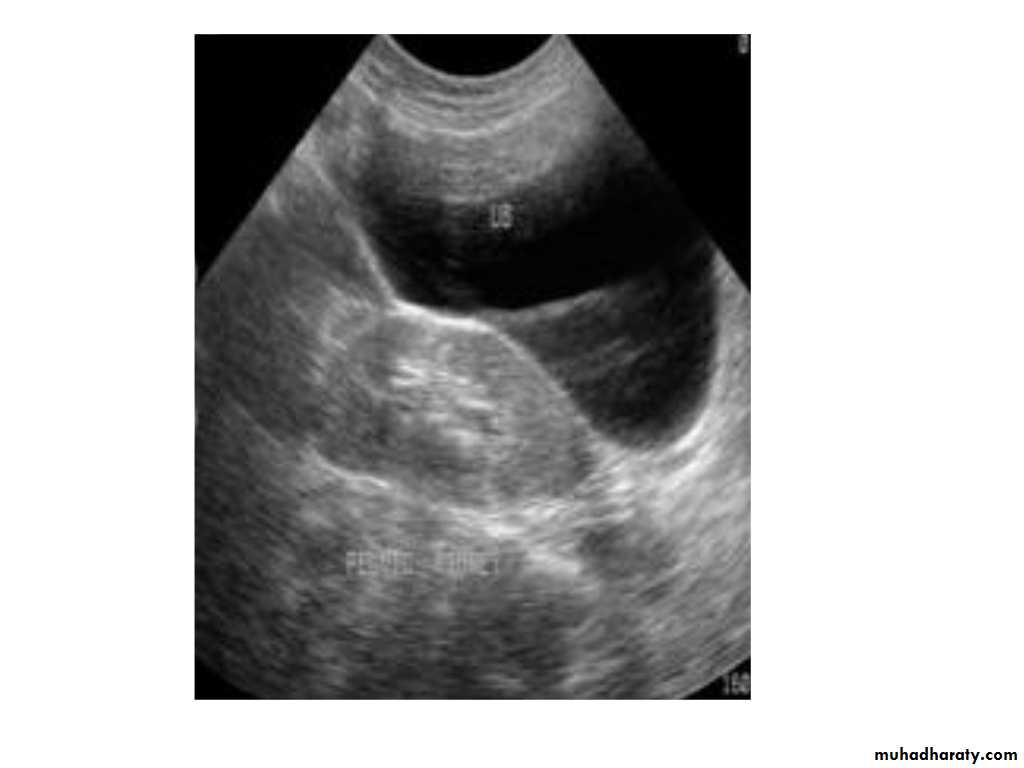

IVU shows

1. The kidneys at low position .2.Close to the spine with long axis parallel to the spine

3. Malrotation manifested by medially directed calyces.

4- The renal pelvis and ureters are anterior and lateral in position.

5- Hydronephrosis and calculi highly associated.